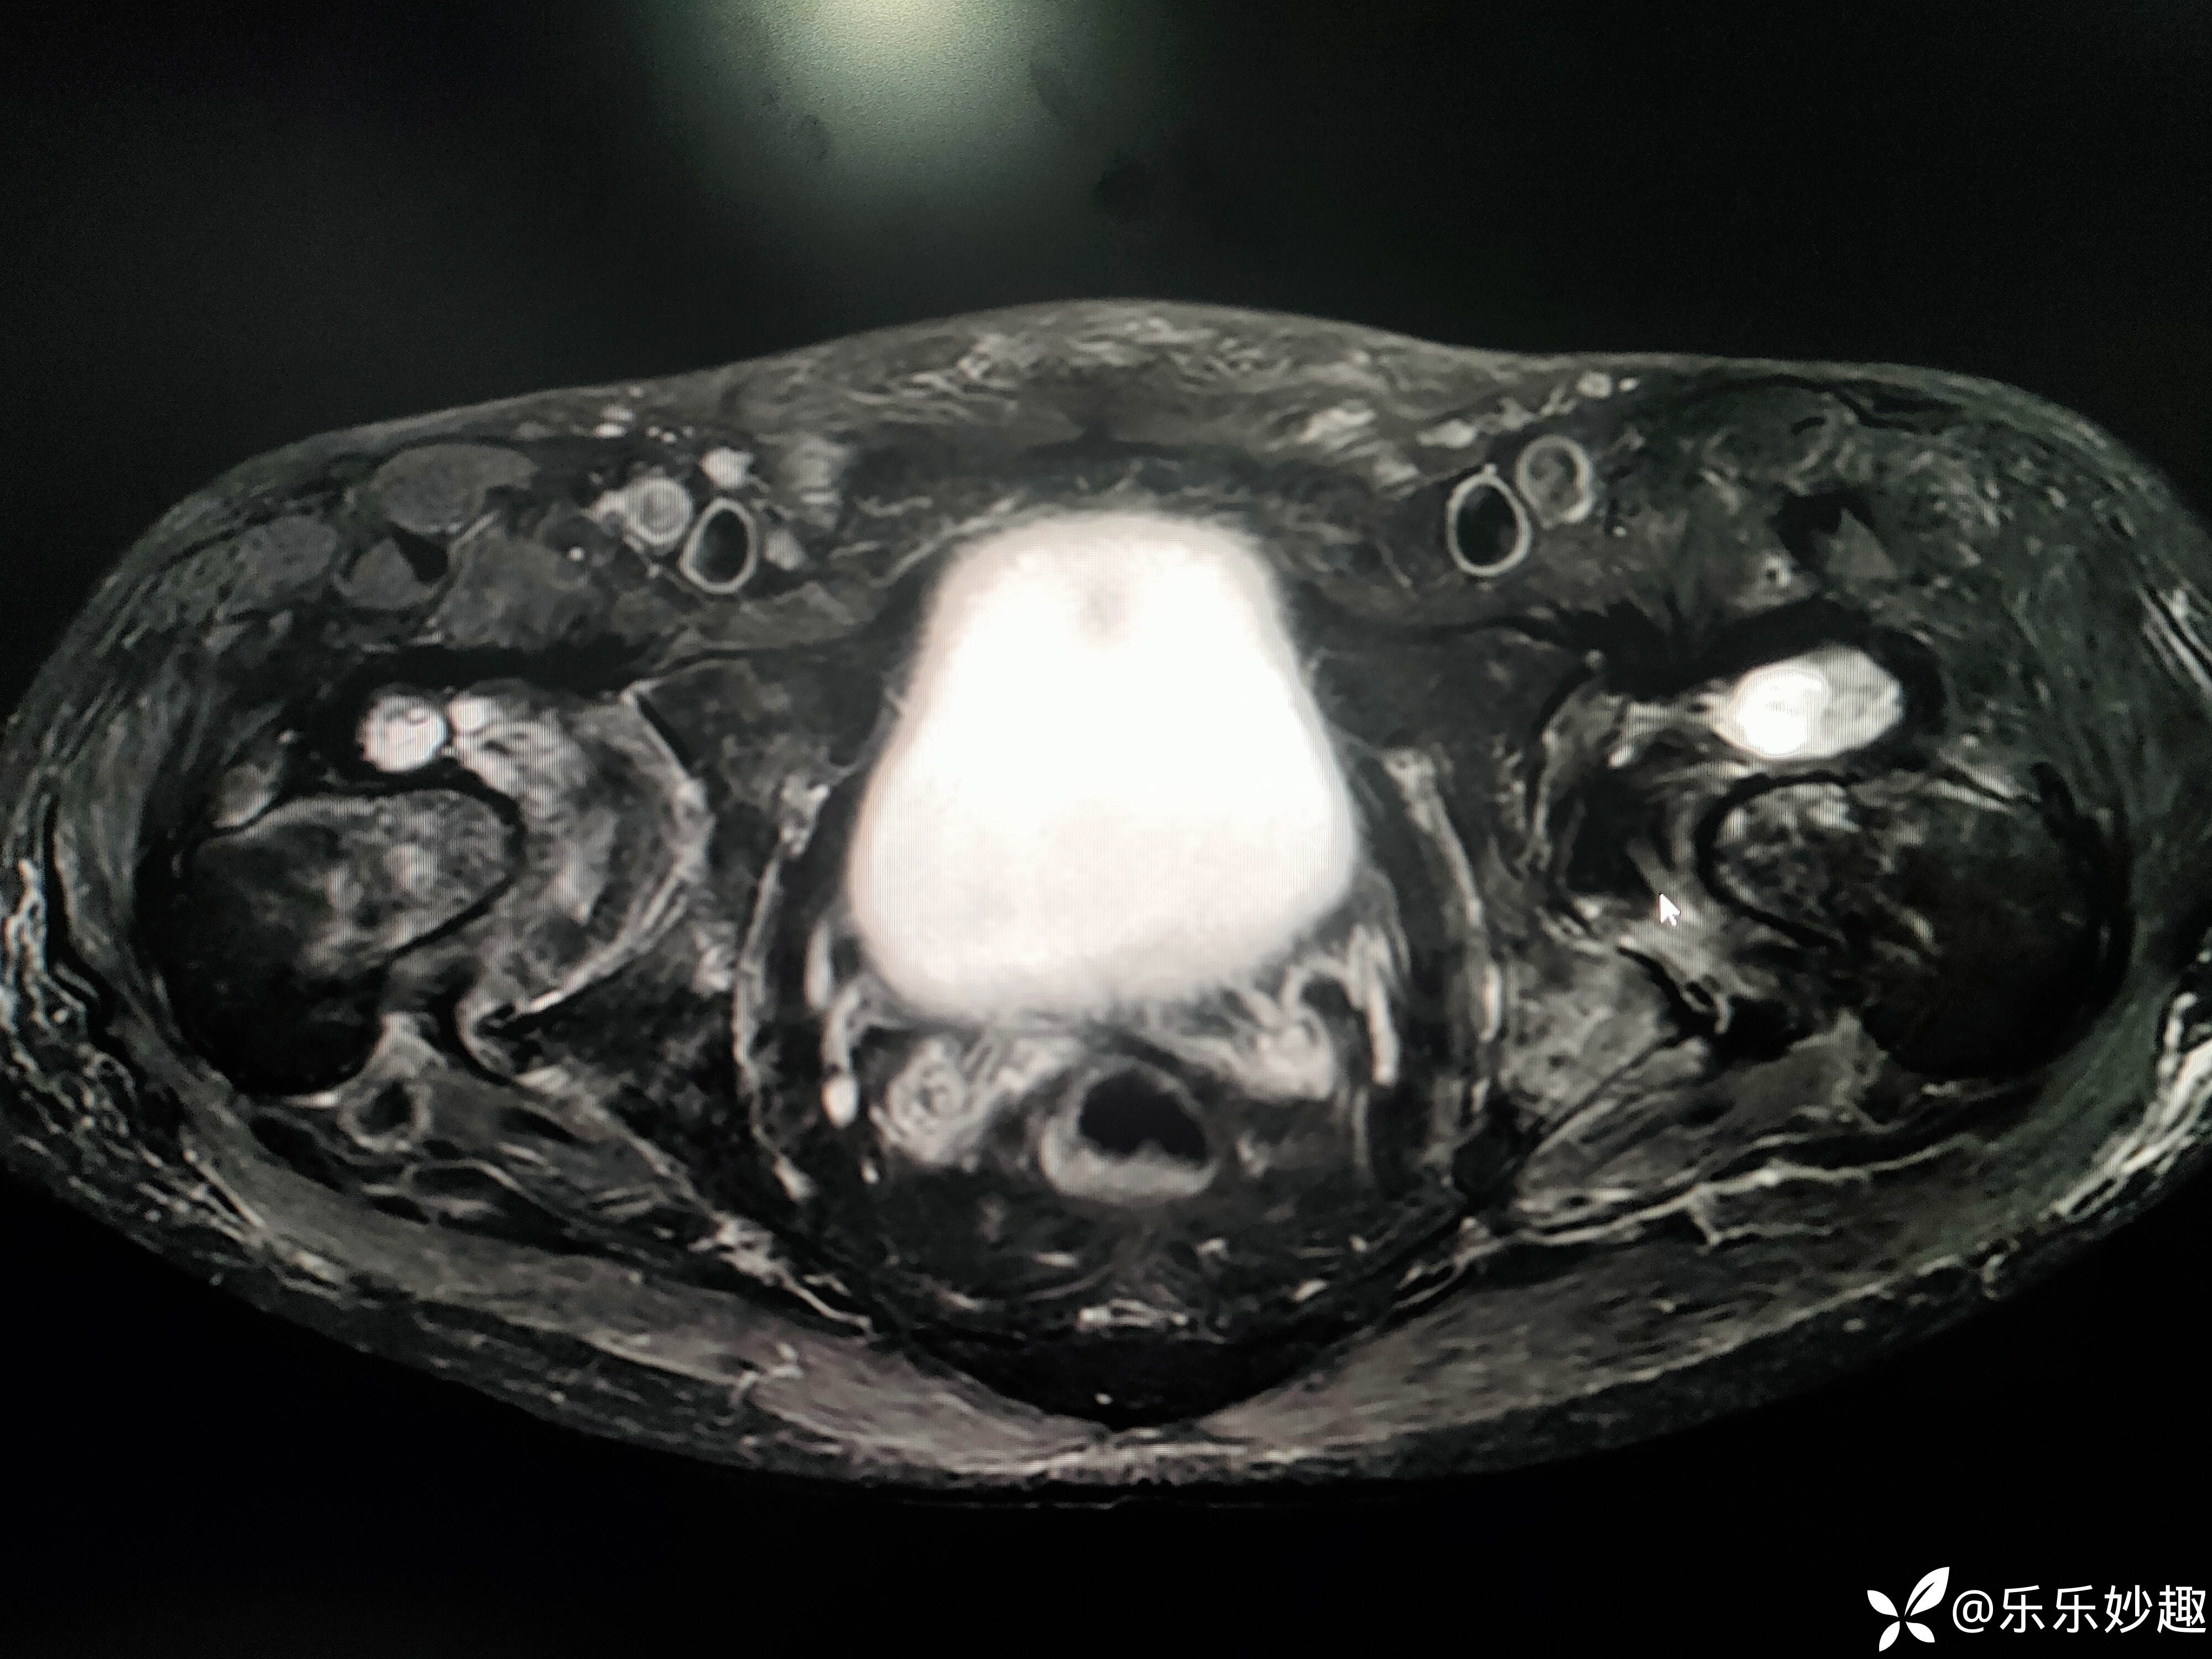

最后做了髋关节MR,见下图